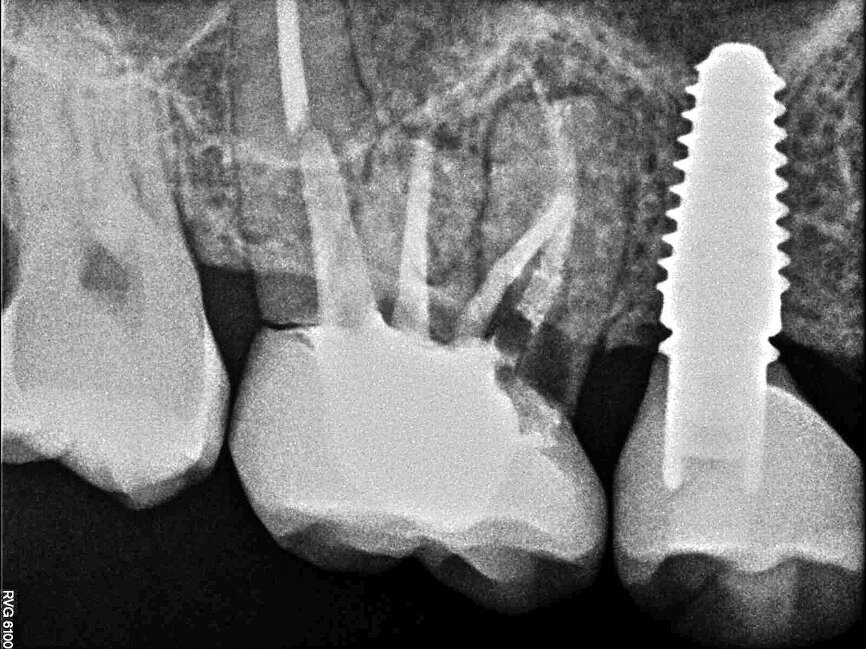

In November 2017, a 39-year-old female patient came to an initial appointment at White Clinic owing to tooth pain (tooth #16). A clinical and radiographic examination were performed, including a periapical radiograph, CBCT scan (Carestream 9500, Carestream Dental), and intra- and extraoral photographs (Figs. 1–3).

In the clinical and radiographic evaluation, it was observed that tooth #16 presented an invasive cervical resorption at the mesiobuccal root. The treatment plan established was dental extraction with immediate implant placement. The tooth had been previously re-treated endodontically and restored with a definitive ceramic crown. Due to the current situation of the tooth, although the protocol in White Clinic is to preserve teeth, it had indication for immediate extraction. Also due to the lack of time, our digital team was not able to produce a surgical guide for the implant placement. Therefore, the treatment plan included a surgical phase and a digital prosthetic phase.

Once the implant bed had been prepared, a 7 × 10 mm implant (AnyRidge) was placed. After placement, the ISQ (Implant Stability Quotient) was measured with a stability meter (Mega ISQ, MegaGen), and the value was 72. According to the ISQ scale, this represents high stability (Fig. 6b). A 10 × 7 mm healing screw (AnyRidge) was placed, along with a plug of A-PRF (advanced platelet-rich fibrin; PRF process by Choukroun) in order to accelerate the healing process, and sutured with 4/0 polypropylene (Hu-Friedy; Figs. 7–10). After the surgical procedure, the White Clinic postoperative protocol was applied: application for eight minutes of the ATP38 laser (Swiss Bio Inov), based on the principle of Low Level Laser Therapy that acts on the cellular metabolism and provides a better and faster postoperative healing. The patient was instructed to use a 0.2% hyaluronic acid gel (Gengigel, Ricerfarma) and 0.1% hyaluronic acid mouthwash (Gengigel First-aid, Ricerfarma) for one week after surgery, with the goal of accelerating the healing process. One week after surgery, the sutures were removed, ozone was used to disinfect the area around the implant, and the ATP38 was applied for eight minutes to promote healing.